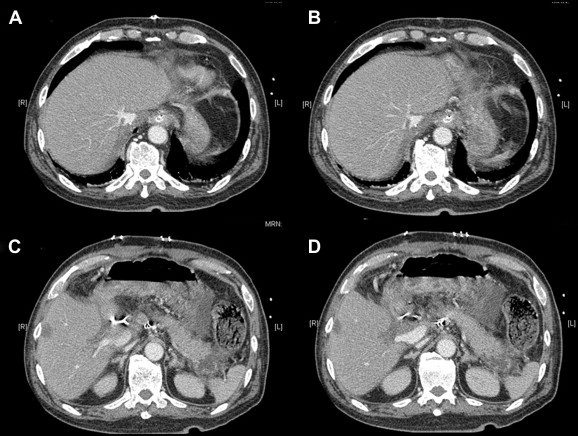

A computed tomography scan 1 week after the operation showed hypertrophy of the liver graft (Fig. 1). Pathology of his excised liver confirmed chronic hepatitis B with cirrhosis. His serum total bilirubin level went down from 582 to 392 μmol/L after the operation and reached a peak level of 550 μmol/L 9 days after the operation. The level gradually returned to normal in 2 months' time. His international normalized ratio returned to normal 11 days after the operation. Daily abdominal drain output was around 500–1000 mL in the early postoperative period, which gradually reduced to an insignificant amount 50 days after the operation. He underwent re-laparotomy for intra-abdominal collection, with peritoneal fluid growing Citrobacter freundii, and gradually recovered. At the time of writing of this article, he has remained alive for 16 months after transplantation.

Computed tomography scan 1 week after the operation showed hypertrophy of the liver graft: (A) small graft hepatic vein, (B) inferior vena cava, (C) small graft portal vein, and (D) normal recipient portal vein.